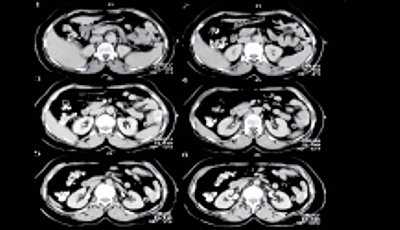

В большинстве случаев (75% больных) опухолевый участок при ТРУЗИ был гипоэхогенным и локализовался в периферической зоне. У одного пациента определялся гипоэхогенный участок, захватывающий периферическую и центральную части. У двух пациентов, используя стандартные методики ТРУЗИ, нельзя было установить границу между нормальной и опухолевой тканью. В нашем исследовании прорастание опухолью стенки мочевого пузыря выявлено у трех пациентов (стадия Т4) (рис.1); прорастание рака предстательной железы в семенные пузырьки определялось у 4 больных (стадия Т3b) (рис.2); капсула прослеживалась на всем протяжении у 11 пациентов с раком предстательной железы (стадия Т2) (рис. 3а); у двух пациентов целостность капсулы была нарушена (стадия Т3а) (рис. 3б). Степень распространения опухоли определяла тактику лечения.

Рис. 1. Тотальное опухолевое поражение предстательной железы на фоне аденомы. Опухоль полностью изоэхогенна ткани аденомы. Поперечный срез предстательной железы.